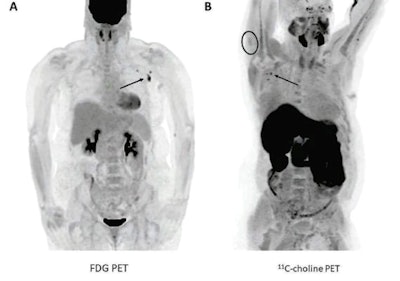

The two finalists in the Best Radiology Image category pit a PET scan of a patient who showed abnormal uptake after getting a COVID-19 vaccine against a series of images demonstrating the power of AI-based image reconstruction for MRI. The finalists were selected through voting on AuntMinnie.com's Facebook page.

The image below is from a study published May 20 in the American Journal of Roentgenology and is one of a number of case reports and studies published this year that show how vaccination for COVID-19 can cause pathology that appears to look like cancer.

PET imaging showed abnormal radiotracer uptake in the lymph nodes of cancer patients after they received COVID-19 vaccinations. (A) A 57-year-old woman with right upper arm melanoma who received the first dose of the COVID-19 vaccine (Pfizer-BioNTech) in the left deltoid 15 days prior to FDG PET/CT. FDG uptake is observed within left axillary lymph nodes (arrow, SUVmax = 9.3). (B) A 62-year-old man with metastatic prostate carcinoma who received the second dose of COVID-19 vaccine (Pfizer-BioNTech) in the right deltoid seven days prior to C-11 choline PET/CT. Image courtesy of the American Journal of Roentgenology.

PET imaging showed abnormal radiotracer uptake in the lymph nodes of cancer patients after they received COVID-19 vaccinations. (A) A 57-year-old woman with right upper arm melanoma who received the first dose of the COVID-19 vaccine (Pfizer-BioNTech) in the left deltoid 15 days prior to FDG PET/CT. FDG uptake is observed within left axillary lymph nodes (arrow, SUVmax = 9.3). (B) A 62-year-old man with metastatic prostate carcinoma who received the second dose of COVID-19 vaccine (Pfizer-BioNTech) in the right deltoid seven days prior to C-11 choline PET/CT. Image courtesy of the American Journal of Roentgenology.The second finalist in the Best Radiology Image category comes from a presentation at the European Congress of Radiology in March 2021 by Dr. Suzie Bash, a neuroradiologist at image services provider RadNet. The image series demonstrates how AI can be used to speed up MRI data reconstruction times while maintaining image quality.